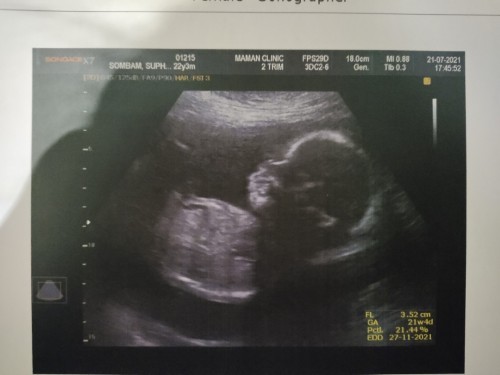

ตอนนี้23week1dayจ้า #ทีมลูกสาว ทีมมิถุนายนจ้า🥰🥰